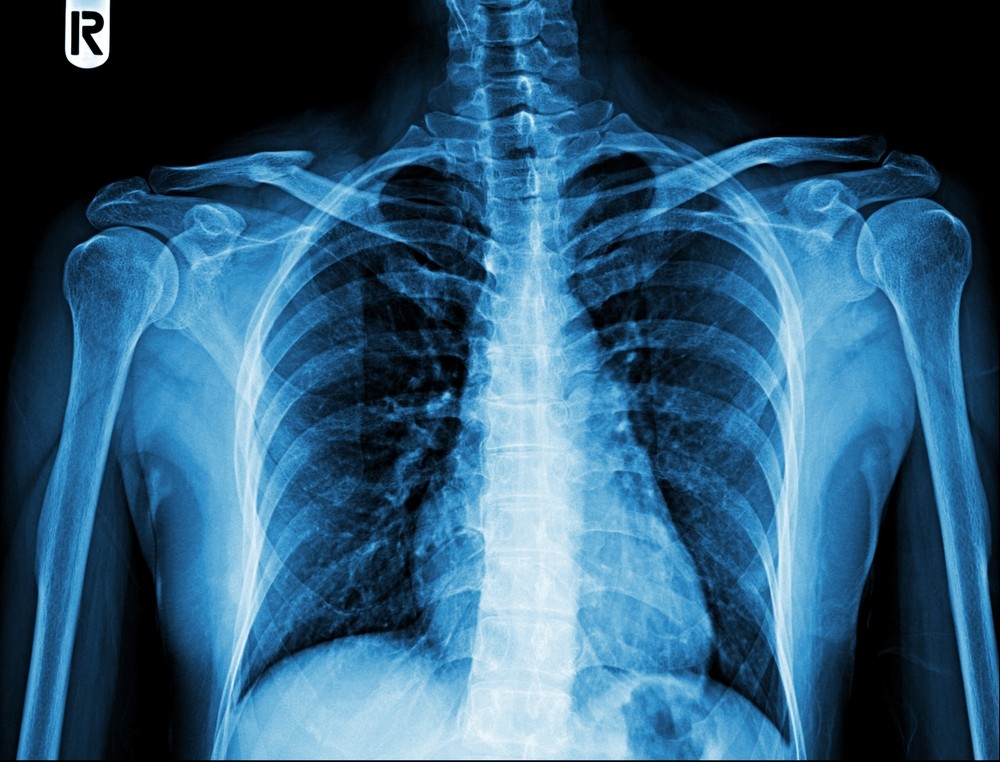

Фотогалерея

Рентген-аппарат